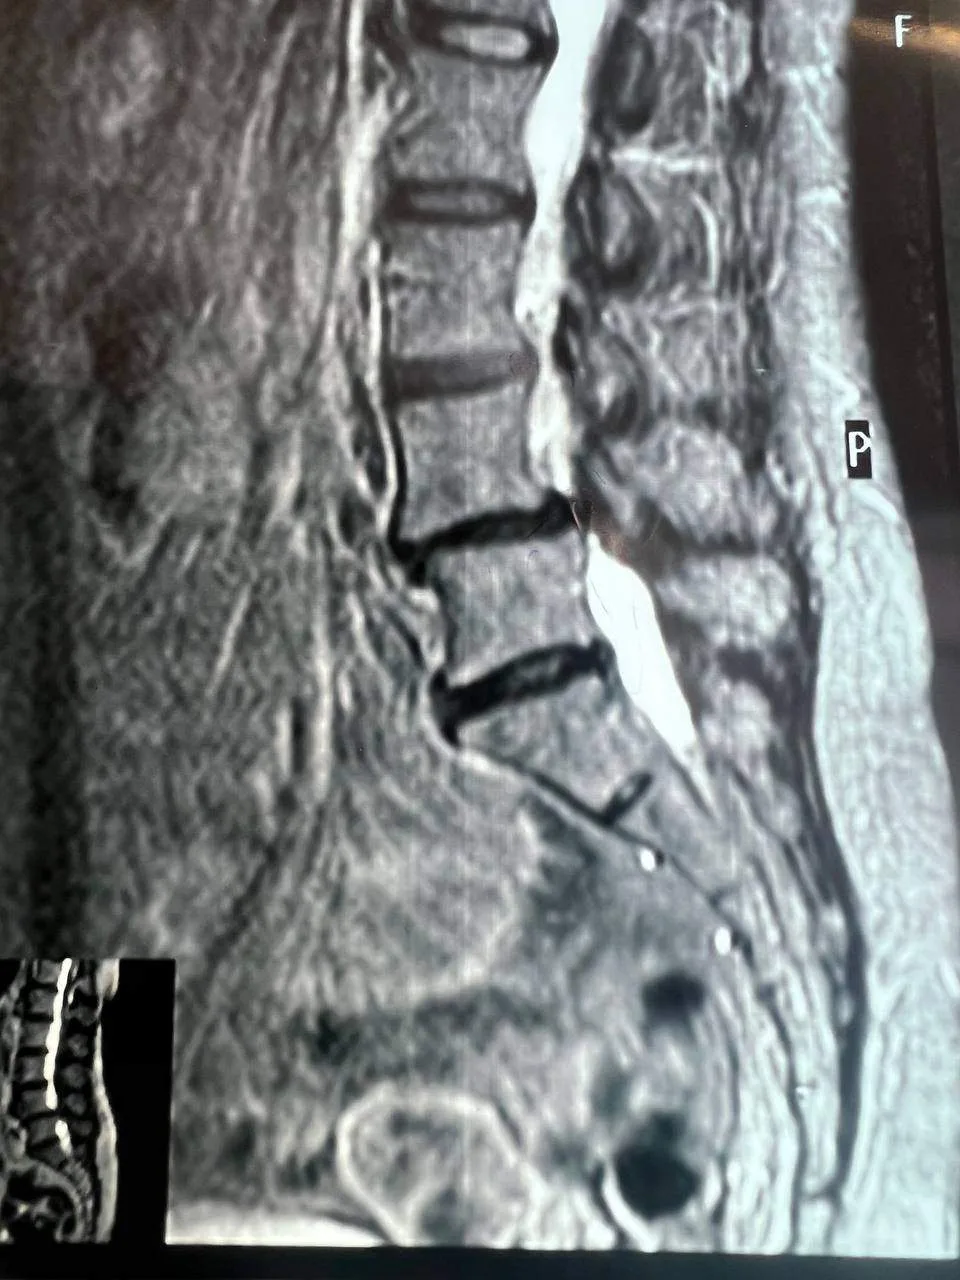

Хирурги выполнили микрохирургическое вмешательство: освободили спинной мозг от сдавления, удалили грыжу и заменили поврежденные диски имплантами. Также исправили смещение позвонка и установили стабилизирующую конструкцию из титановых винтов и балок.

Операцию провела бригада под руководством нейрохирурга Евгения Дронова. Послеоперационный период прошел без осложнений. На следующий день пациентка уже вставала и передвигалась без боли. Функции нервов восстановились за неделю, походка нормализовалась. На восьмой день женщину выписали под наблюдение невролога.